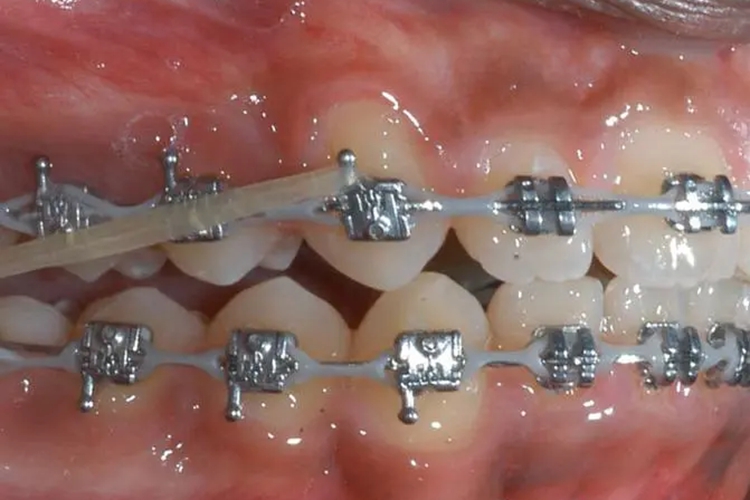

牙齿正畸

由于施力过大,牙齿移动距离过长,力作用于牙齿时间过长等原因,均可使牙根吸收;部分人群牙齿对力较敏感,牙齿在受力后,可引起特发性牙根吸收。

正畸时出现牙根吸收的情况,应减小力值,拉长间隔时间加力。若有轻微的牙根吸收,一般无需特殊处理,待牙齿移动至新的位置后会逐渐恢复正常。